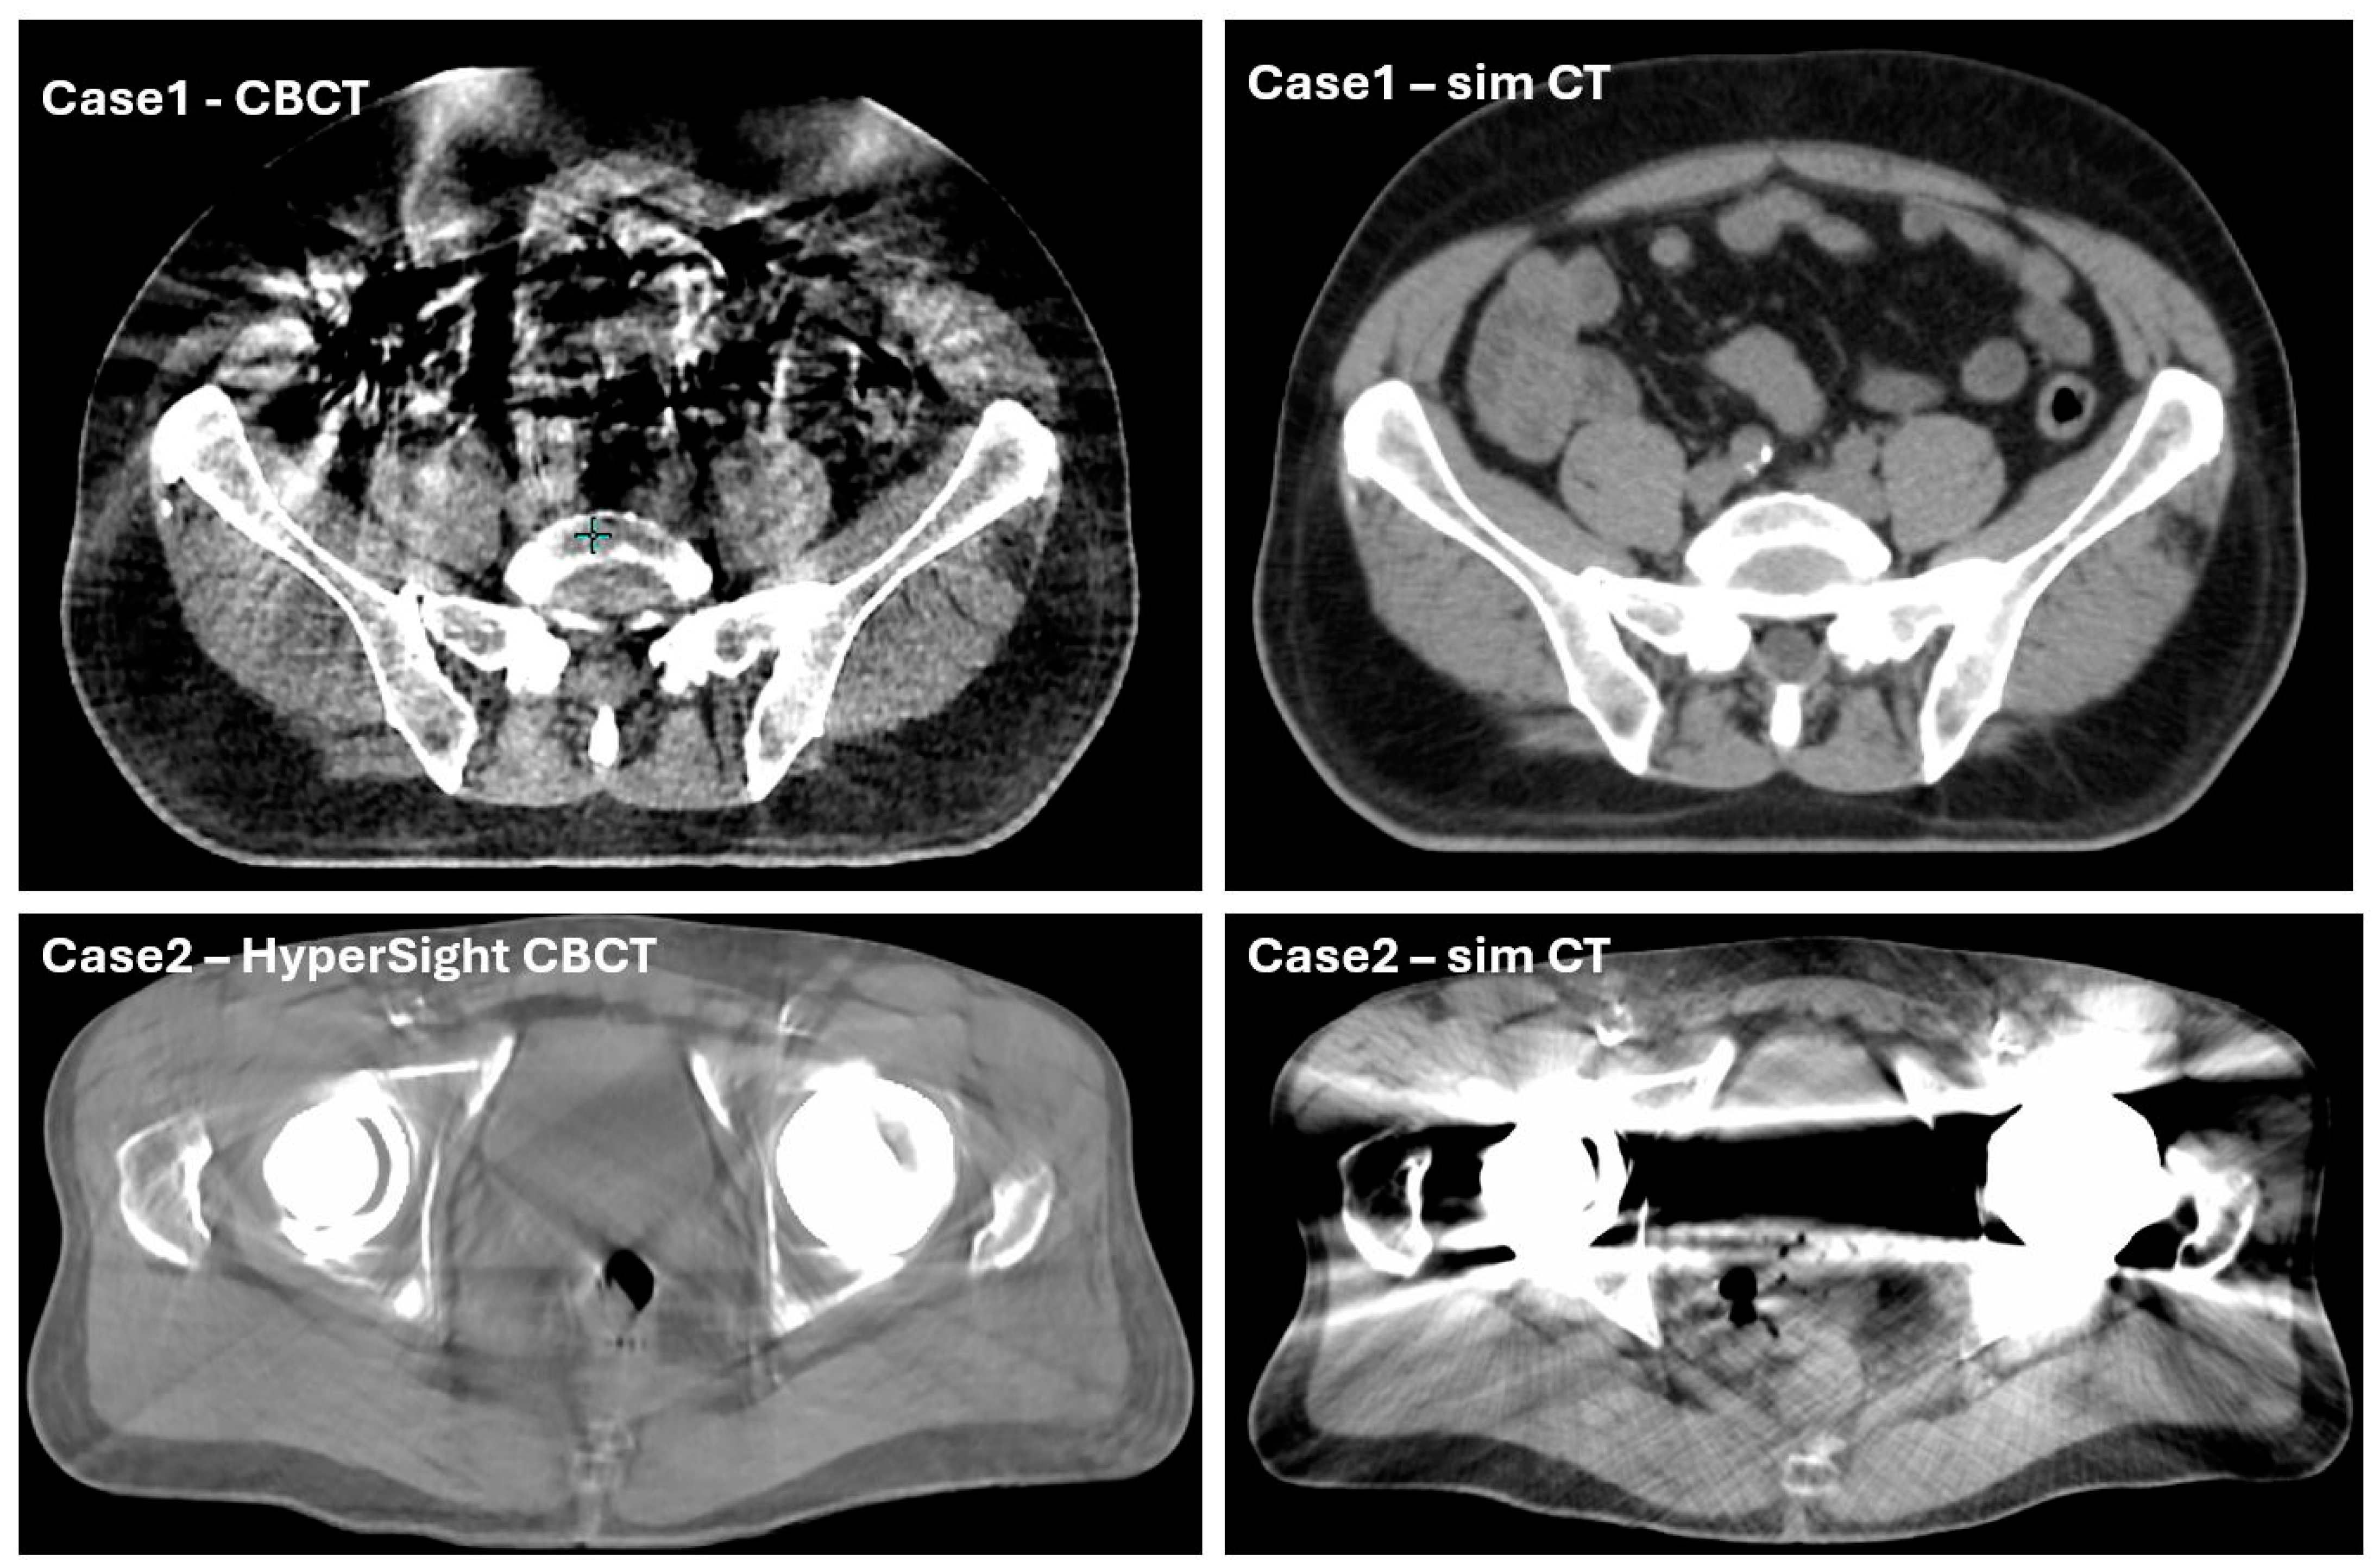

3.2.1. System-Driven Issues